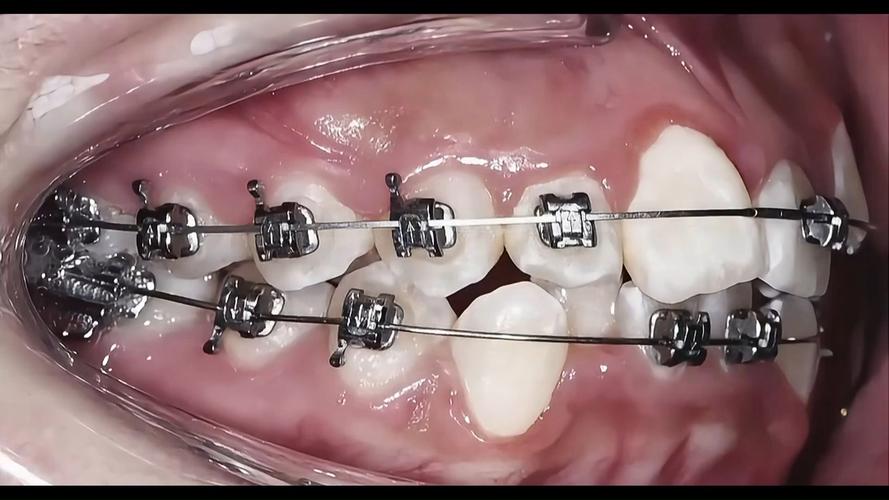

| 传统固定矫正 | 矫正力稳定、性价比高、适用范围广(复杂病例) | 美观度差、口腔清洁难度大、舒适度较低 | 各年龄段闭锁合患者,尤其需拔牙或颌骨调整者 |

| 自锁托槽矫正 | 摩擦力小、矫正效率高(复诊间隔延长4-6周) | 价格较高、托槽体积较大可能影响舒适度 | 对复诊时间有要求、追求高效矫正的患者 |

传统矫正需通过弓丝结扎使牙齿移动,逐步排齐牙齿、打开咬合(解除前牙闭锁)、调整后牙咬合关系;隐形矫正则需每1-2周更换一副牙套,通过持续轻力实现牙齿移动,此阶段需严格遵循医嘱,避免食用过硬、黏性食物,防止托槽脱落或牙套损坏。